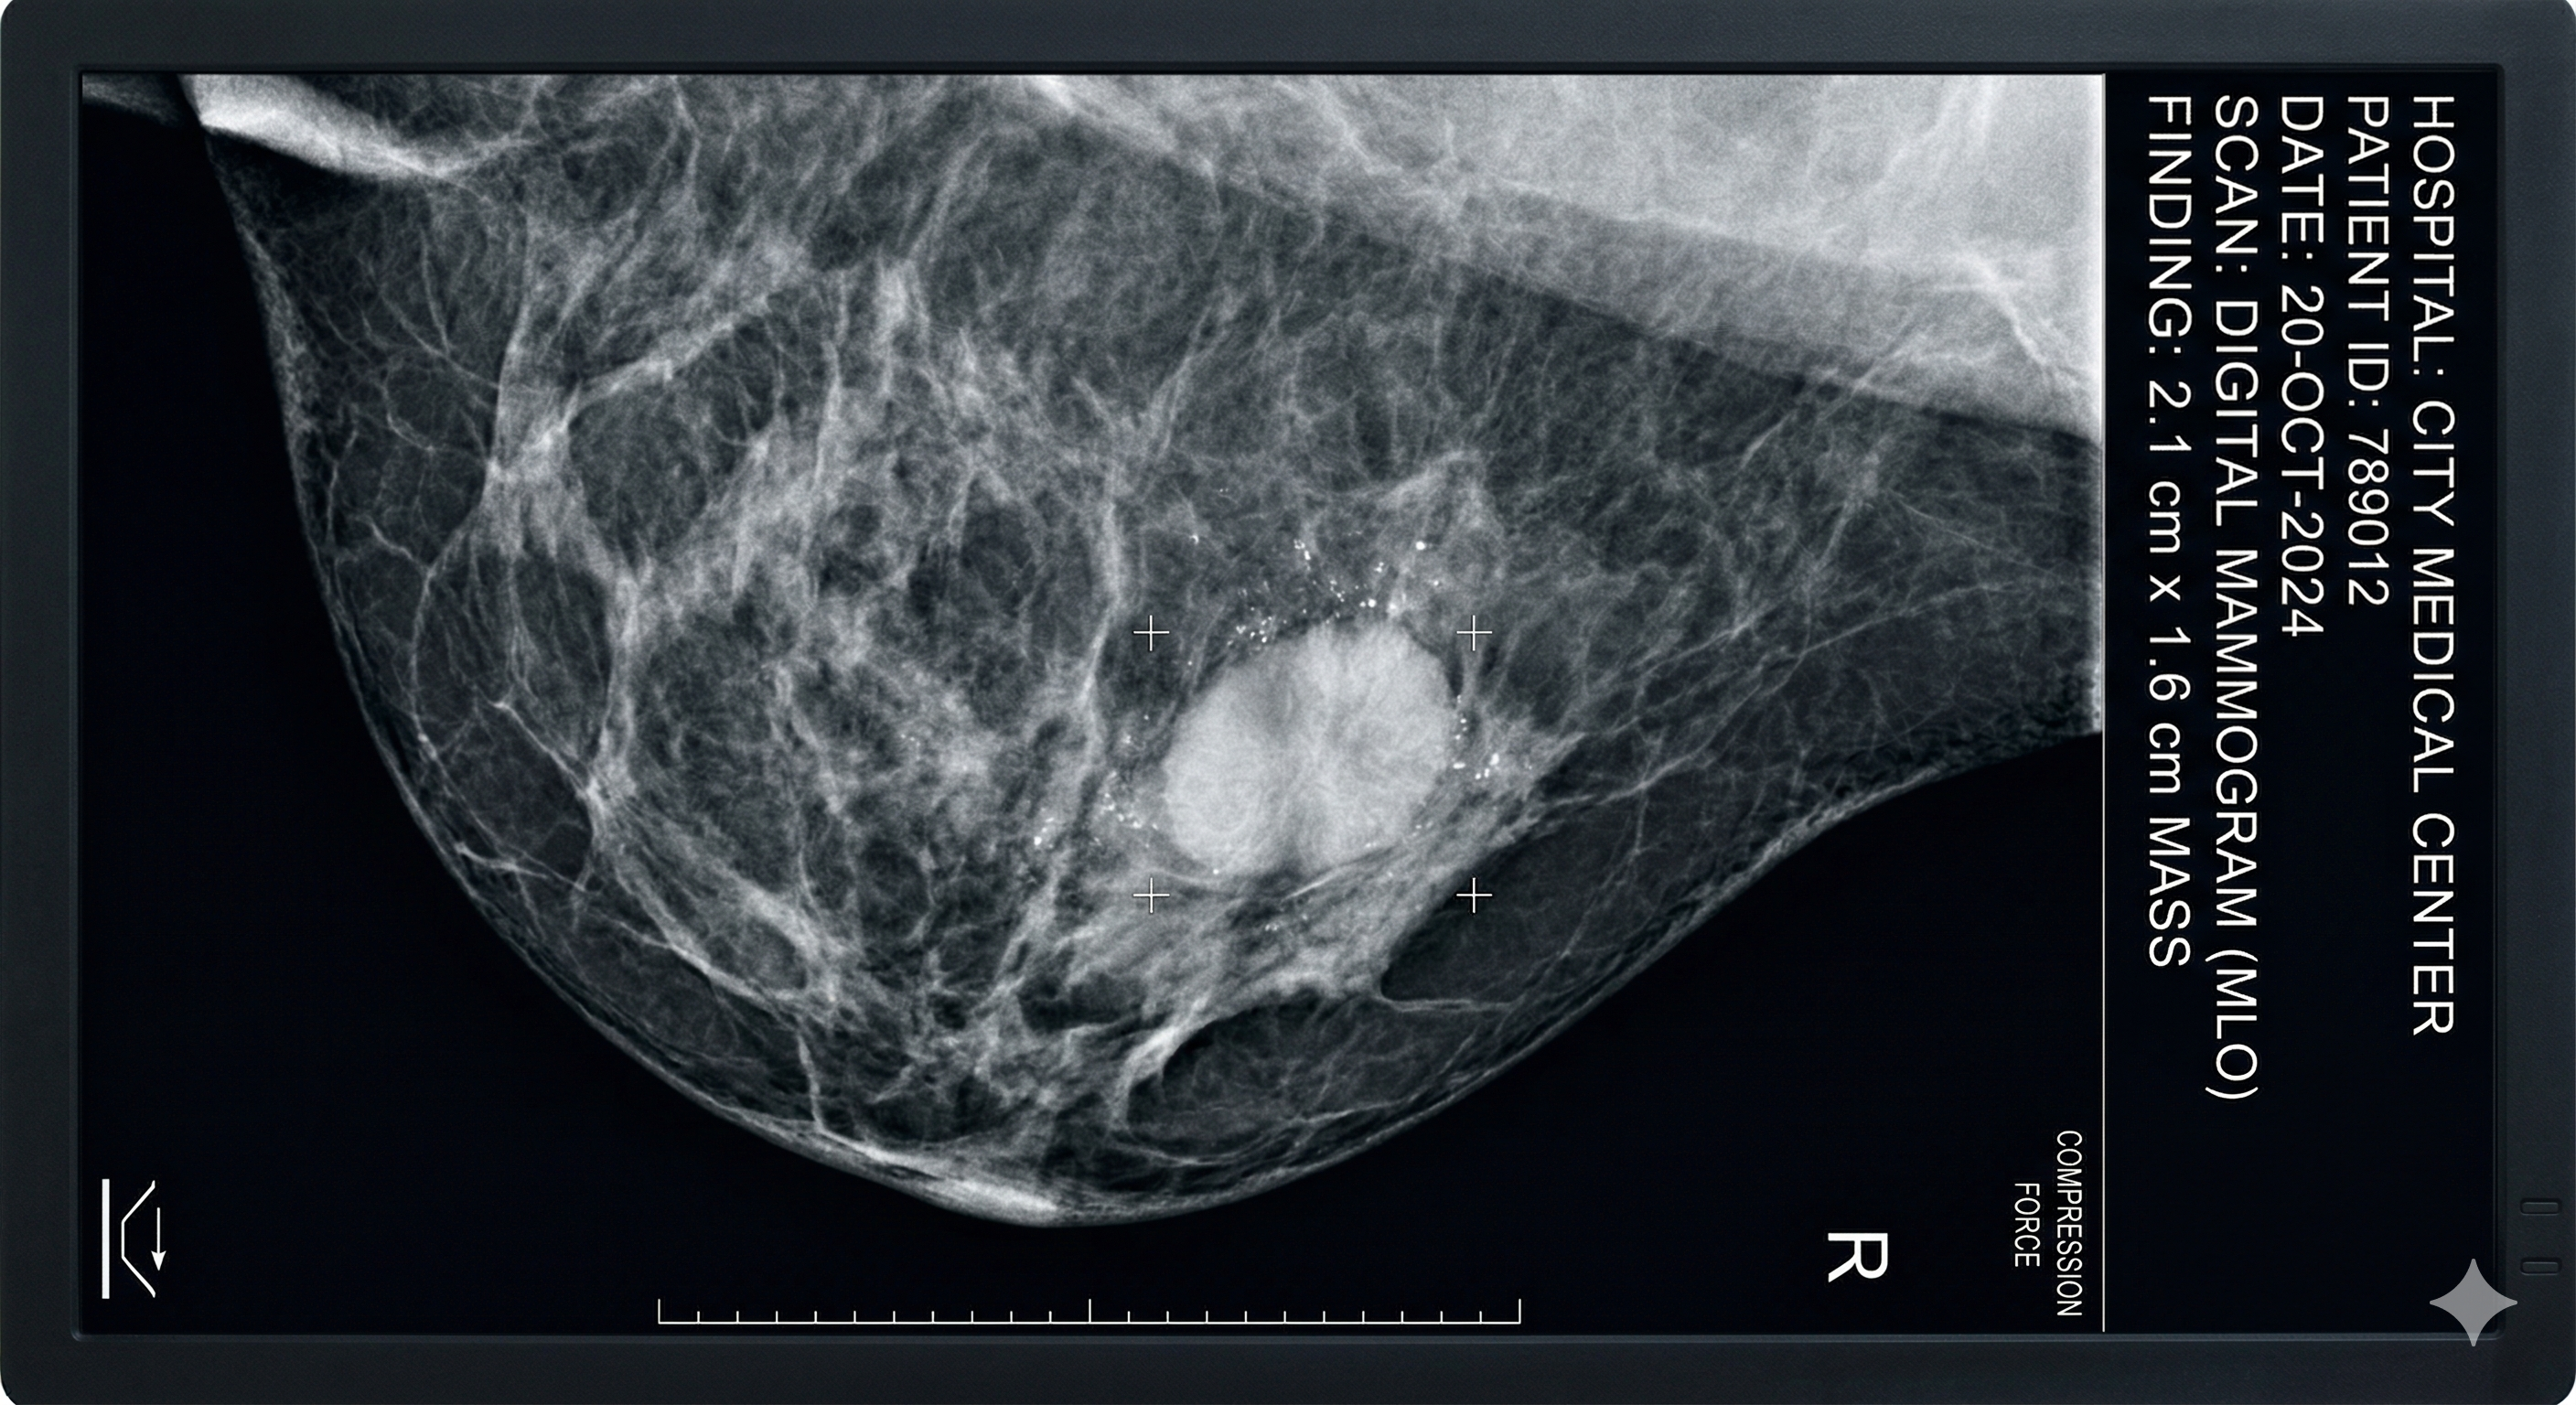

Mammograms are one of the most widely used tools for breast cancer screening. They work by using low-dose X-rays to capture images of the breast and identify unusual changes in tissue. While they are highly valuable, they are not flawless.

One of the biggest limitations of mammography is how it performs in dense breast tissue. Dense tissue appears white on a mammogram the same color as many abnormalities, including tumors. This makes it significantly harder to distinguish between normal tissue and something that may need further attention.

Younger individuals, in particular, are more likely to have dense breast tissue, which means a mammogram alone may not provide a complete picture. Even in less dense breasts, some lumps can be too small, too subtle, or located in areas that are difficult to capture clearly with X-ray imaging.

So when a lump is present but not visible on a mammogram, it doesn’t mean the lump isn’t real. It means the imaging method may not be the right one to detect it.